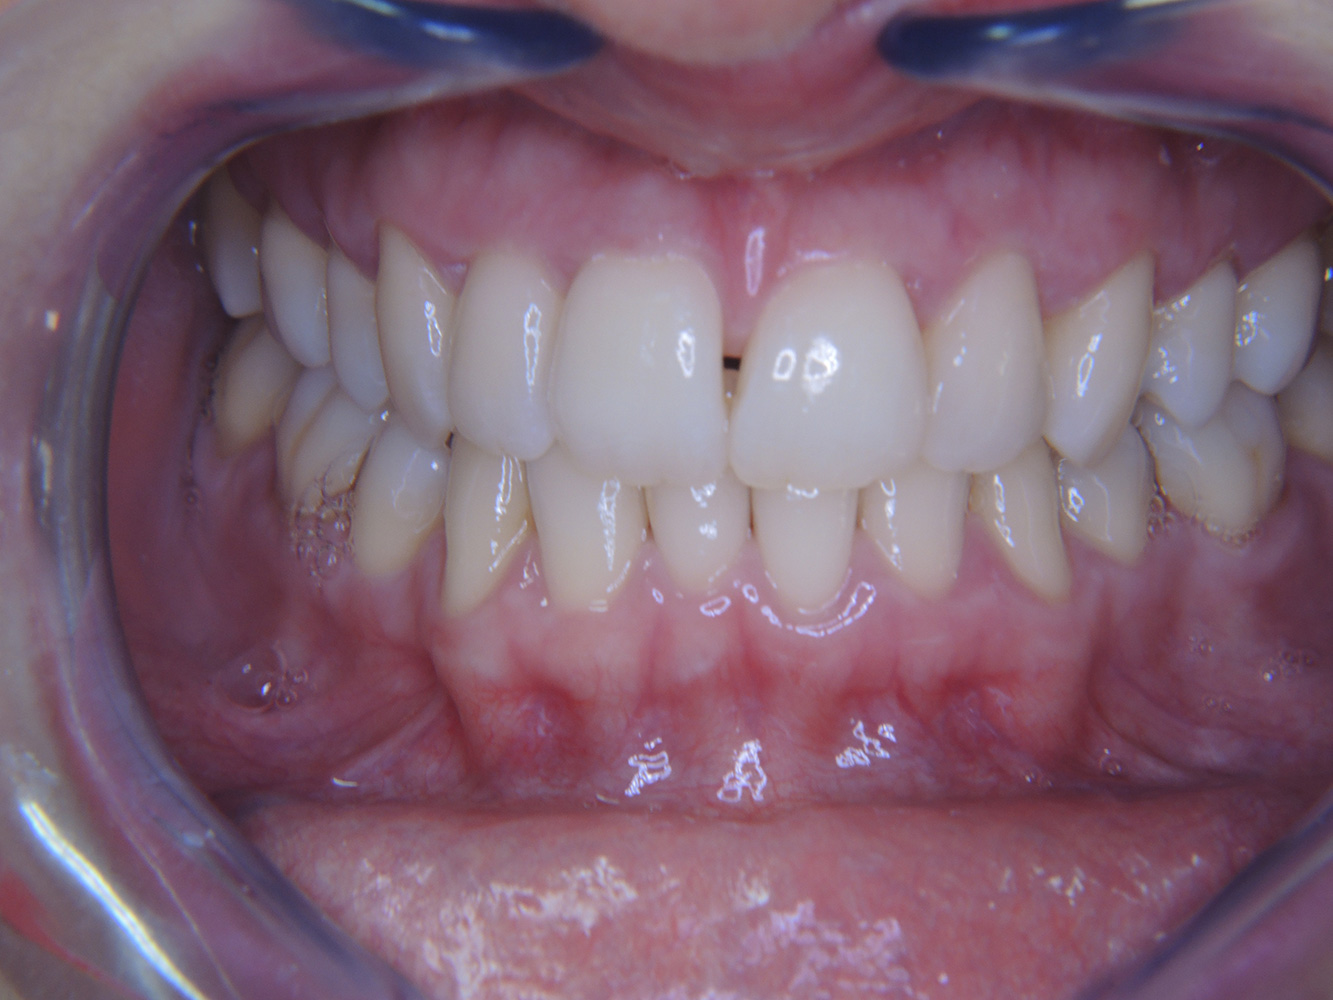

Una paziente diabetica di 51 anni con una buona igiene orale si presenta per una seduta di prevenzione. I valori di glicemia sono stabili con HbA1c = 6,2%, per cui si ritiene che la sua condizione possa essere sufficientemente gestita con la metformina (un farmaco per il trattamento del diabete). La paziente non presenta restauri esistenti o precedenti patologie orali. Sulla base dei referti disponibili si può constatare una gengivite nonostante una condizione altrimenti stabile.